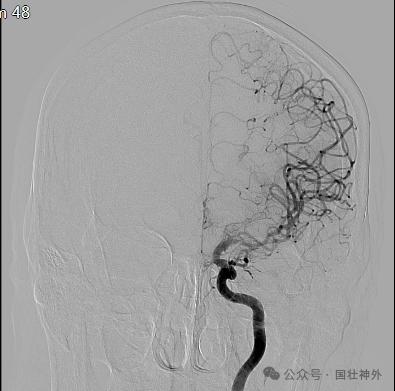

31岁的龚小姐半年前便时常感觉右侧手脚乏力使不上劲,有时甚至完全无法动弹,工作生活受到了很大影响。对龚小姐而言,烟雾病导致的症状主要为肢体乏力,但神经外科蔡利主任注意到,她在交流过程中说话常常词不达意,也无法很好地控制声调,且生活中总爱忘事,用眼时也常感觉模糊不清,“这说明烟雾病依然在影响着她,病情没有根本性改善”。通过进一步的DSA检查发现,龚小姐的双侧颈内动脉存在严重的闭塞和脑底毛细血管增生,其中颈内动脉的供血量占脑部血液的80%,不解决闭塞状况其症状很可能会再次发作。“从脑血流灌注成像图可以看出,她的大脑血液灌注量低,迫切需要获得足够血液。”蔡主任说。

烟雾病侧支循环分级:①DSA显示大脑后动脉(PCA)与大脑前动脉(ACA)或大脑中动脉(MCA)的侧枝循环状况:a.PCA的顶枕支与ACA吻合(pPCAACA),供应ACA和PCA区皮质为1分,由PCA的后胼周动脉供应超过中央沟为2分;b.PCA的题前支与MCA吻合为1分;C.DPCA→MCA,仅至MCAM4段供血区浅层为1分;供血深入侧裂,即MCA的M3段供血区为2分;至闭塞部位,即MCA的M1或M2近端供血区为3分(图1)。②采用Suzuki分级进行评估前循环闭塞部位的烟雾状血管对基底节区供血代偿:SuzukiI-IV级分别评为6-1分。最后,总分等于①+②。总分1-4分、5-8分和9-12分分别表示侧支循环差、一般和好。